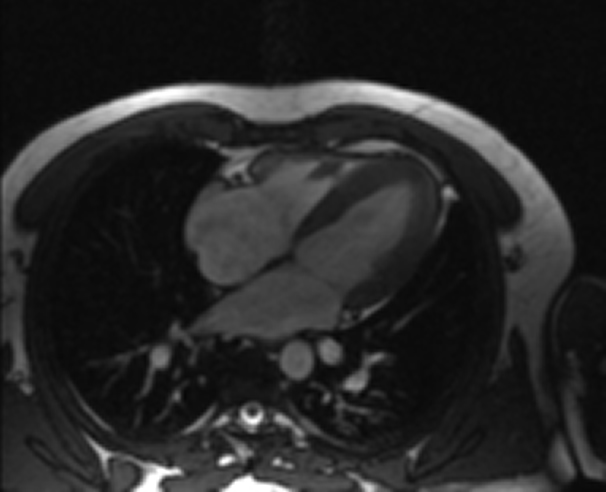

RM Cardíaca

Descripción

Es una prueba diagnóstica no invasiva que obtiene información morfológica y funcional del corazón y las estructuras adyacentes; de esta manera se pueden diagnosticar diferentes patologías congénitas y adquiridas, o bien realizar controles en pacientes con patología previa ya conocida. En la gran mayoría de casos es necesario el uso de contraste intravenoso (gadolinio) para completar el estudio, un tipo de contraste que raramente produce reacciones adversas. Durante la prueba, el técnico le pedirá varias veces que aguante la respiración durante 10-15 segundos para obtener las imágenes lo más claras posible. No se necesita preparación previa alguna por parte del paciente. La duración de la prueba es de aproximadamente 45-60 minutos. Está contraindicada en pacientes con marcapasos; el paciente debe avisar si es portador de implantes metálicos y/o clips quirúrgicos.